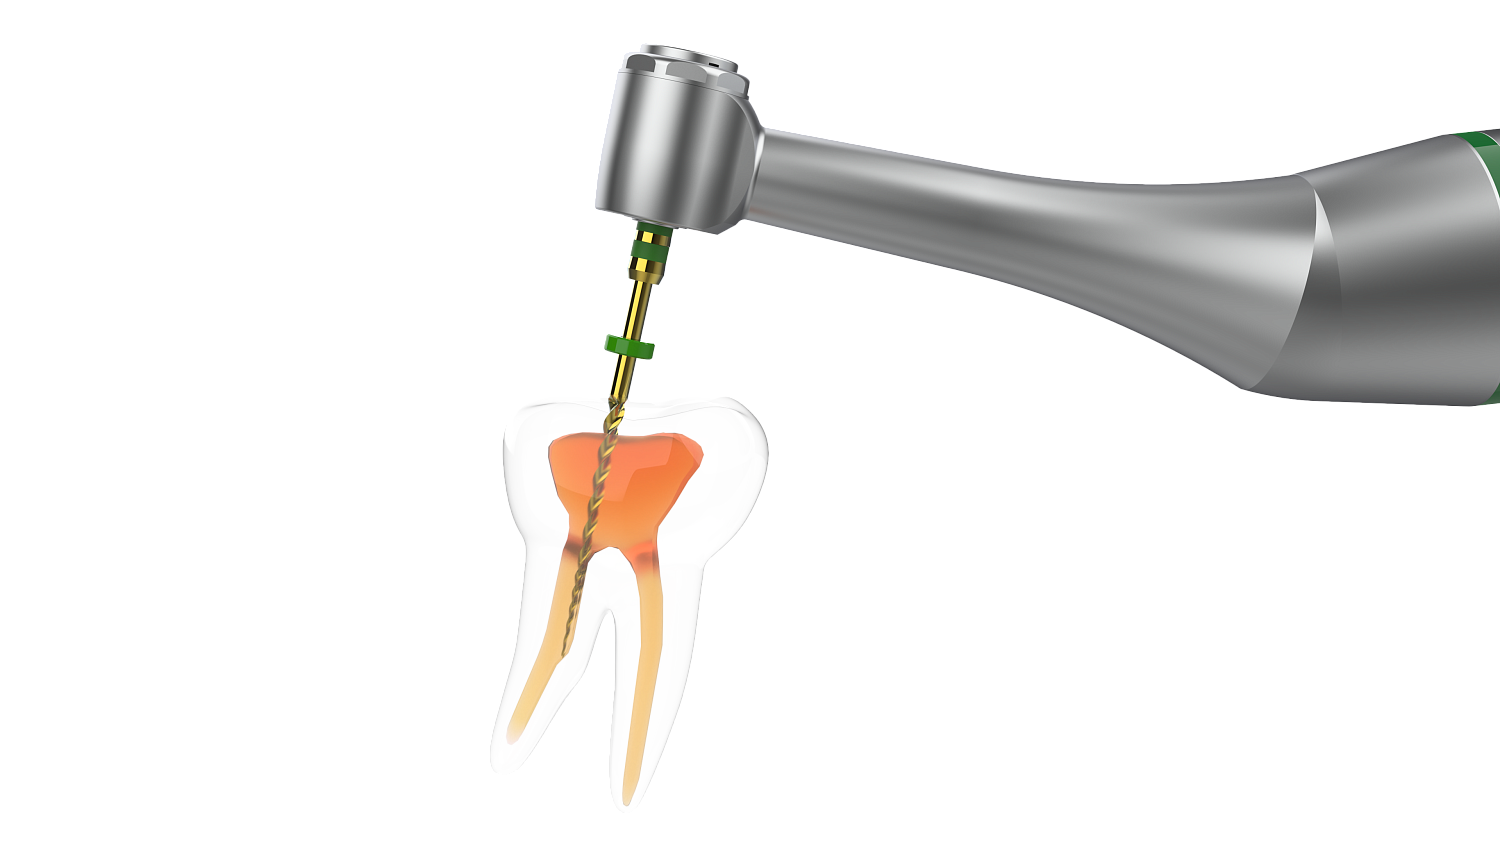

Диапазон регулировки крутящего момента - 0,6 - 3,9 Н/см. Диапазон регулировки скорости - 100 - 1000 об/мин. 5 встроенных программ: - Р1 - Р3 - режим непрерывного вращения. - P4 - режим возвратно-поступательного вращения. - P5 - режим возвратно-поступательного вращения OGP. Эргономичное и удобное использование: легкий вес (104 г), малый шум. Миниатюрная головка 8 х 10,2 мм |

| Препарирование корневого канала |